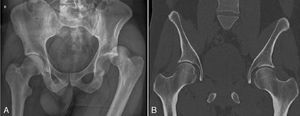

Es trasladado a Santiago en ambulancia, donde se realiza reducción cerrada satisfactoria en pabellón con maniobra de Allis, con imágenes de control que muestran adecuada reducción sin otras lesiones asociadas (fig. 1). Es dado de alta al día siguiente en buenas condiciones, para regreso a su país de origen.

Es evaluado en un servicio de urgencia de montaña, donde se observa la extremidad inferior izquierda acortada, en rotación interna y aducción, sin déficit neurovascular al examen (fig. 2).

Luego de analgesia, se obtienen radiografías y se diagnostica luxación posterior de cadera izquierda, que fue reducida en pabellón con maniobra de Allis en forma satisfactoria una vez trasladado a Santiago. Una resonancia magnética posterior a la reducción mostró desprendimiento anterior y posterior del labrum, pero no fue necesaria una intervención quirúrgica.